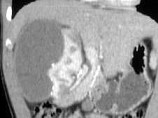

- 单项选择题患者19岁,肾性高血压, 根据图像,对其原因的评价, 正确的诊断为 ( )

A、嗜铬细胞瘤

B、肾动脉狭窄

C、肾癌

D、Page(佩奇氏)肾

E、以上都不是